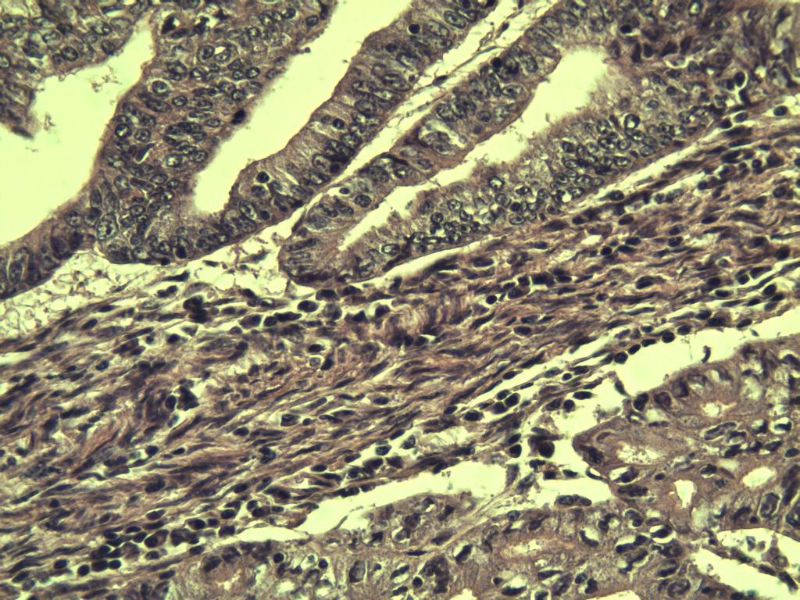

女,57岁,全切子宫一个,宫体体积 9 × 8 × 7 cm3,肌壁厚 2.5 cm,内膜菲薄,部分区域增厚达 0.4 cm(约3*2.5cm区域)。 请问各位老师  这个可以诊断子宫内膜癌了吧?      深肌层没有看到浸润。

患者因"发现下腹部包块1月多"入院  宫体体积 9 × 8 × 7 cm3,肌壁厚 2.5 cm,内膜菲薄,部分区域厚 0.4 cm(约3*2.5cm)。宫颈结构不清,长约 2.5 cm,表面欠光滑。临床诊断宫颈宫腔积液.

宫内膜样腺癌

筛状、迷路样结构

间质消失或者纤维性间质

子宫内膜样腺癌

高分化子宫内膜样癌。浸润浅肌层(深度<1/3肌层)。根据FIGO2009分期,子宫内膜癌局限于内膜层和<1/2肌层,都属于IA期。二者处理不再区别对待。